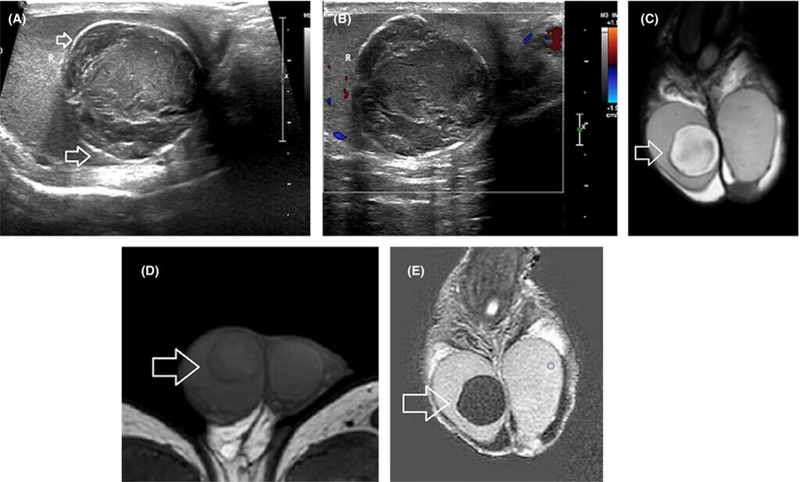

Các cấu trúc của bìu và vùng chậu sẽ được hiển thị rõ ràng trên phim chụp cộng hưởng từ không dùng thuốc cản quang. Bên cạnh đó, các tổn thương có thể được phát hiện ra tại các khu vực này nếu có.

Tương tự như phương pháp chụp cộng hưởng từ bìu không dùng thuốc cản quang, hình ảnh thu được bằng phương pháp chụp cộng hưởng từ có dùng thuốc cản quang cũng hiển thị thị rõ cấu trúc của bìu và phát hiện ra các tổn thương (nếu có) với đặc điểm ngấm thuốc cản quang.